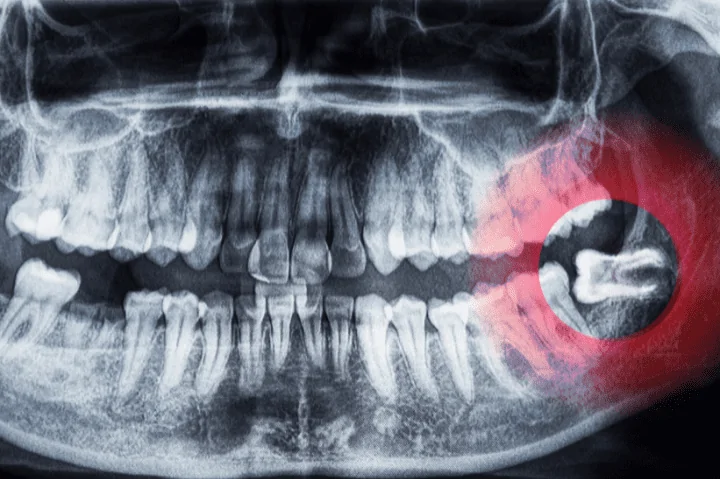

What Are Wisdom Teeth and Why Do They Often Need Removal?

Wisdom teeth (third molars) typically emerge between ages 17 and 25. Because most mouths don’t have enough room to fit them properly, wisdom teeth often lead to:

• Impaction (trapped under the gums)

• Pressure on nearby teeth

• Swelling or infection

• Jaw or gum discomfort

Not everyone needs their wisdom teeth removed, but if they begin causing problems—or are likely to—we may recommend extraction to prevent future issues. At Tooth Harmony, we use detailed imaging to evaluate your wisdom teeth and provide guidance based on your individual needs.